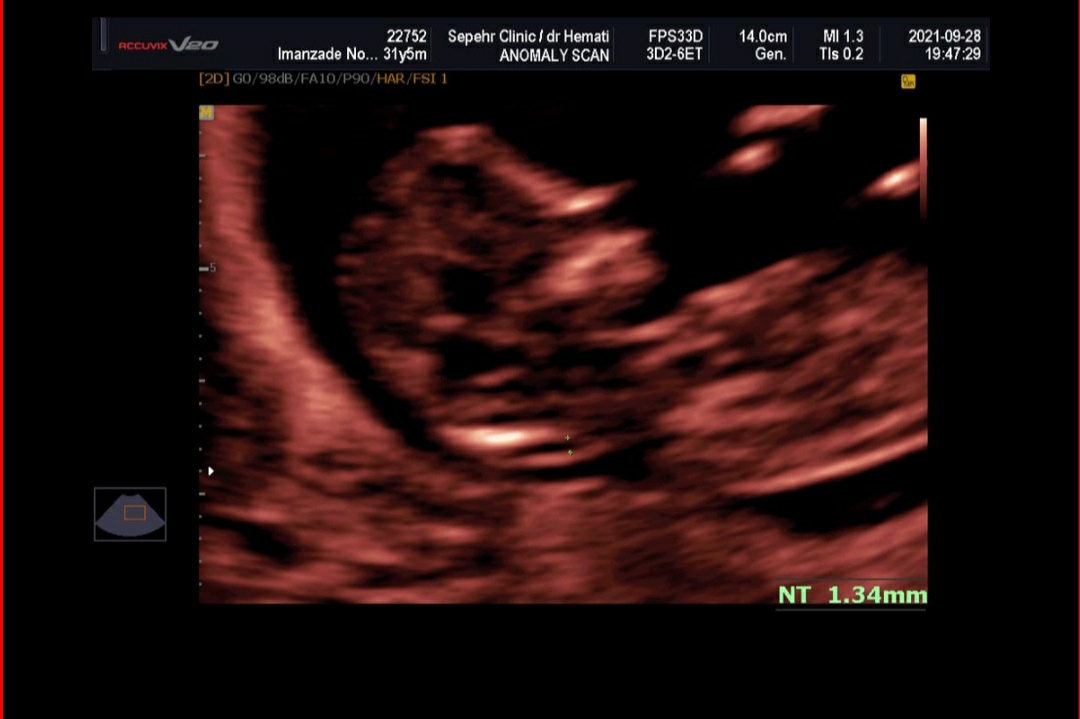

سلام به روی گلتون مامان جان

خیلی خیلی مبارکتان باشد ریسک محاسبه شده برای سندروم های ژنتیکی تریزومی ۲۱ و تریزومی ۱۸ و 13 همگی در محدوده کم خطر قرار داشته و منفی هستند. در حال حاضر نیاز به هیچ بررسی دیگری نیست جان دلم و صرفاً در هفته هجده بارداری مانند تمامی مادرانی که در محدوده کم خطر قرار دارند، سونوگرافی آنومالی اسکن برای ارزیابی ساختارهای بدن جنین و همچنین آزمایش Ntd screen برای ارزیابی اختلالات لوله عصبی (این بررسی ضرورت جدی انجام ندارد و در صورت صلاحدید پزشکتان درخواست گردد) را انجام دهید،، سونوگرافی هم خوب است❤️